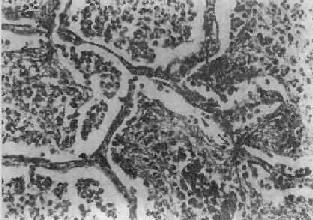

图9-19 支气管肺炎

图中见灶状实变的肺组织,肺泡内充满以中性粒细胞为主的炎性渗出物;病灶中有发炎的细支气管